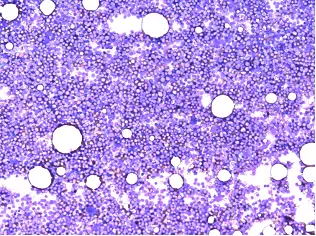

造血幹細胞が様々な細胞に成長していくことを分化と呼びます。急性リンパ性白血病では、リンパ球への細胞の分化の途中で異常が起こり、細胞が成長をやめてしまいます。この成長をやめた細胞(白血病細胞または芽球と呼びます)が骨髄中で増殖し、骨髄を占拠します。その結果として正常な血液細胞が作られなくなり、治療をしなければ、短期間でヒトの命を奪うことになります。

血液検査のみでは診断ができないため、骨髄検査が必要になります。骨髄検査ではメイギムザ染色法という染色法による細胞形態観察を基本として芽球を含めた幼若な細胞から成熟した細胞まで細かく分類します。現在広く使用されているWHO分類では骨髄中の芽球の数が20%以上で急性白血病と診断します。そのうち、ペルオキシダーゼ染色という方法で陽性となる芽球が3%未満である場合を急性リンパ性白血病3%以上である場合は急性骨髄性白血病と診断します。